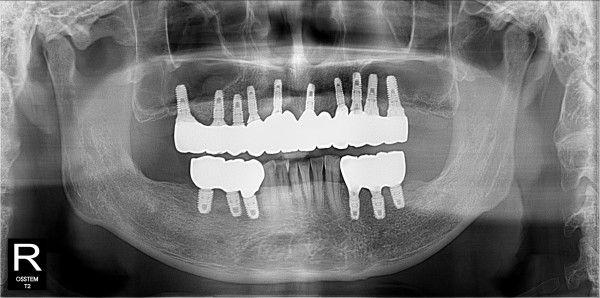

구치부 임플란트